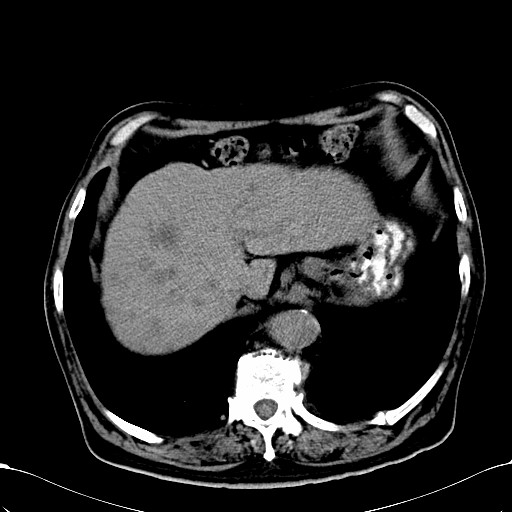

标题: CT28270:胰管扩张,肝多发占位 [打印本页]

标题: CT28270:胰管扩张,肝多发占位

患者,男,75岁。

考虑胰腺钩突癌并肝内转移,建议强化明确。

1)考虑胰头癌并肝脏多发性转移;建议行ct增强扫描检查。2)胃窦癌?建议行胃镜检查。

肝脏多方低密度结节,边缘模糊,考虑多发转移,胰管明显扩张,建议增强扫描钩突情况

肝脏多发低密度灶,胰头似呈低密度,胰管扩张,建议增强,

胰管显著扩张,但胆总管未见扩张征象,不太符合胰头占位!考虑慢性胰腺炎.胃窦占位并肝内转移可能!mrcp胃镜增强一起上!